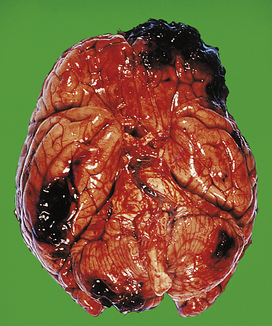

Examination of the CSF by lumbar puncture is essential in each case; the main CSF changes in the CNS infections are listed in Table 26.6. The CSF in bacterial meningitis usually contains many organisms, although these are sometimes detected only on culture. In fatal cases, pus is present in the cerebral sulci and around the base of the brain, extending down around the spinal cord (Fig. 26.13).

image

Fig. 26.13 Bacterial meningitis: basal exudate. In this example of pyogenic meningitis due to Escherichia coli, a dense acute inflammatory exudate is present around the brainstem, cerebellum and adjacent structures at the base of the brain. Obstruction of the fourth ventricle exit foramina resulted in acute hydrocephalus in this case.

The meningeal and superficial cortical blood vessels are congested, often with small foci of perivascular haemorrhage. The CSF is usually turbid, even in the ventricles, which often show signs of acute inflammation with fibrin deposition. Common complications of bacterial meningitis are: